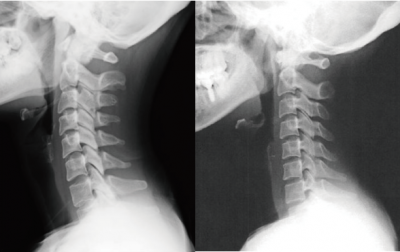

その後、半年くらい経過して思い当たる原因も無く首に違和感を感じるようになり、その後時々頭痛も感じはじめ、病院を受診して検査を受けるとレントゲンでストレートネックになっているといわれ、痛み止めの薬で様子をみてくださいということでした。

体の歪みは右に捻れ、頸椎はストレートネックなっている感じがあり、歪みからは首の痛みと頭痛を感じやすい状態になっていました。